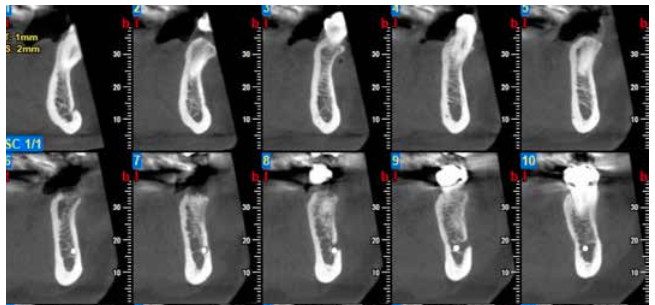

Actitud terapéutica frente a una reabsorción interna perforante

Atendiendo a la localización de la reabsorción radicular, ésta puede ser clasificada en externa o interna. La reabsorción interna es relativamente poco frecuente, y su etiología y patogénesis no está todavía del todo clara. Este artículo muestra la complejidad de un incisivo central superior con una reabsorción interna inflamatoria perforante. El diagnóstico definitivo lo hallamos a través del examen tridimensional, que confirmó la extensión y comunicación con la superficie externa radicular.

Aunque como podremos ver a lo largo de la exposición del caso clínico, la ayuda del microscopio nos permitió abordar el caso con mayor seguridad. En todo momento pudimos eliminar el tejido inflamatorio y preparar el conducto de manera adecuada. La obturación en este tipo de casos supone un reto para el endodoncista, siendo éste, mayor cuando se realiza únicamente de manera ortógrada. Para la obturación realizamos una técnica descrita en la literatura, sellando la zona apical a la reabsorción con gutapercha adaptada mediante condensación vertical; la zona reabsortiva con material biocerámico y, por último, la zona coronal con gutapercha inyectada.

Se realizó un 3D a los 26 meses para una nueva evaluación de la zona reabsortiva, y así evaluar el estado óseo alrededor de la misma. La paciente se presenta totalmente asintomática sin signos clínicos y con buena salud de los tejidos periapicales.